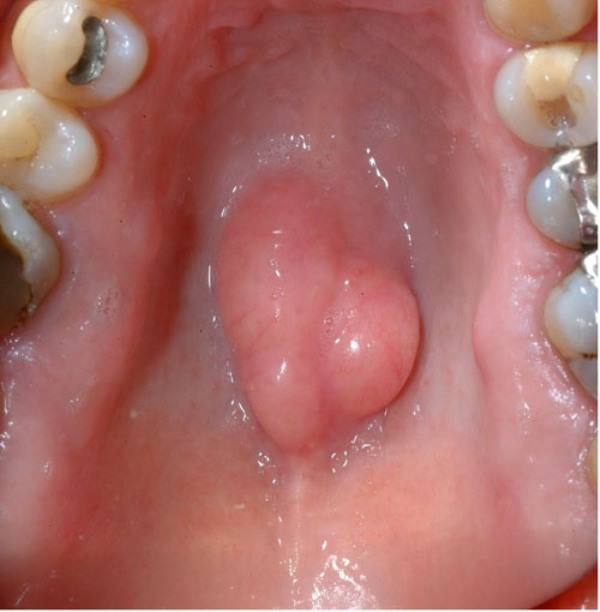

Torus Palatinus (Bump on Roof of Mouth), Causes, Diagnosis, Removal …